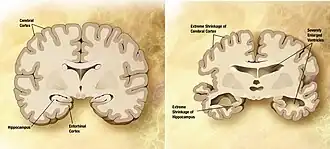

Atrophie corticale

La maladie d'Alzheimer est caractérisée par une perte de neurones et de synapses dans le cortex cérébral et certaines régions subcorticales. Cette perte anormale entraîne une atrophie des régions affectées, incluant le lobe temporal, pariétal et une partie du Lobe frontal et du gyrus cingulaire[62]. Le cerveau peut ainsi perdre 8 à 10 % de son poids tous les dix ans, contre 2 % chez un sujet sain. L'atrophie corticale s'accompagne d'une dilatation des ventricules cérébraux et des sillons corticaux ainsi que d'une perte neuronale affectant particulièrement le système cholinergique (noyau basal de Meynert, septum, cortex entorhinal, amygdale et hippocampe).

Les études utilisant l'IRM et le PET scan ont documenté une réduction de certaines régions spécifiques chez les personnes atteintes de la maladie d'Alzheimer lorsqu'elles progressent d'un trouble cognitif léger vers une maladie d'Alzheimer, en comparaison des images de sujets sains âgés[63],[64].

- l'atteinte de l'hippocampe joue sur les processus de mémorisation : enregistrement, restitution et organisation des souvenirs;